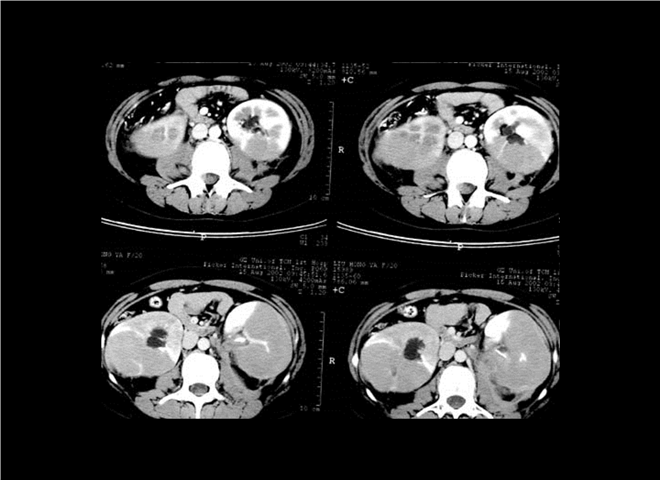

13_CT增强扫描